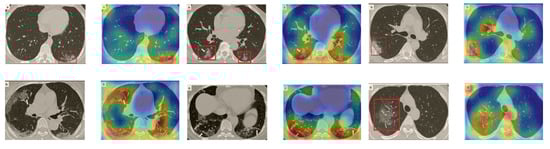

5.5.2. The Grad-CAM Visualization

In order to make our models more transparent and visually interpret the results, we provide the Grad-CAM localization maps generated by using different models. We utilized the CT images from COVID-19 class from the test set for each dataset, and highlight the important regions considered for the prediction. Figure 13 shows examples of CT images from the SARS-CoV-2 CT dataset and their localization maps. Interestingly, in most of the cases, our InceptionV3 model correctly classified them as COVID-19 cases and highlighted the regions of abnormalities in the CT scans, which are important for the model’s decision.

Figure 13.

Grad-CAM visualizations for examples of CT images from the SARS-CoV-2 dataset. Our InceptionV3 model correctly classified them as COVID-19 and localized the most relevant regions used for its decision. The first, third, and fifth columns show CT images with COVID-19 findings, whereas the second, fourth, and sixth columns represent their corresponding localization maps generated by Grad-CAM.